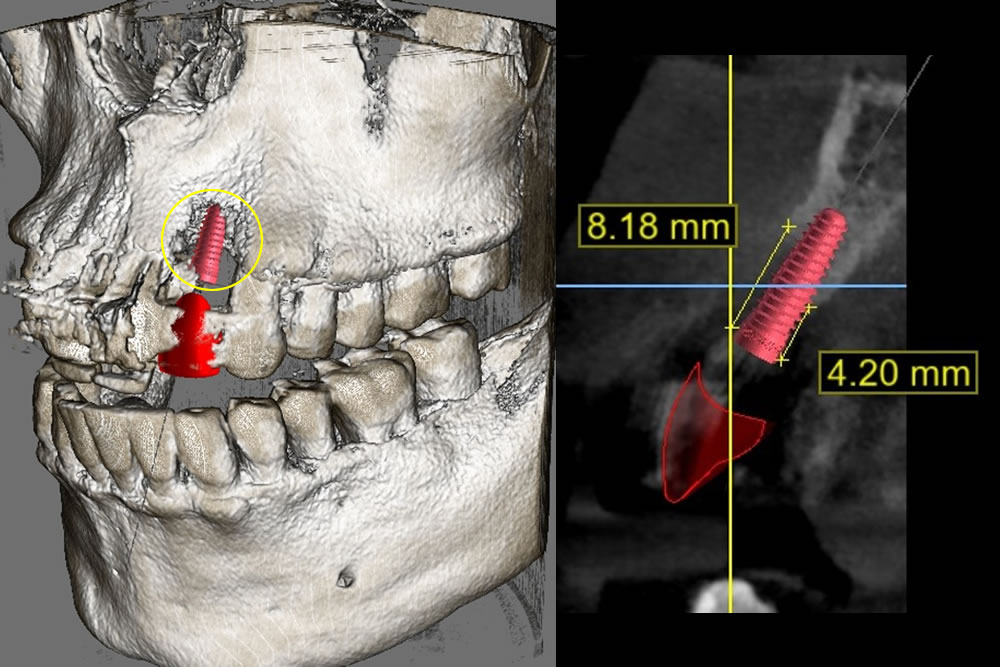

シミュレーション

インプラントのネジ部分が露出しないようにしなければなりません。広範囲に骨を作ることができるのか、人工的に作った骨は長期的に信頼できるものか(溶けてなくなってしまわないか)など不安・懸念点がありました。

上記の問題点に加え、骨を作る量が多いので治療期間も非常に長くなることを患者様へお伝えしました。相談の結果、インプラントができないわけではありませんでしたが、数多くの困難な点、術後の不安定性などを総合的に考慮し、ブリッジで咬み合わせを回復することになりました。